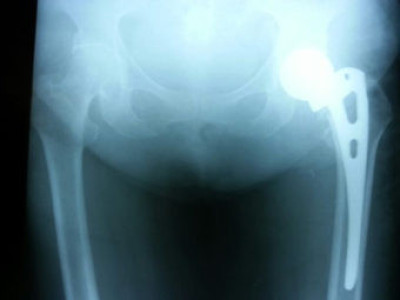

Prótesis de Cadera